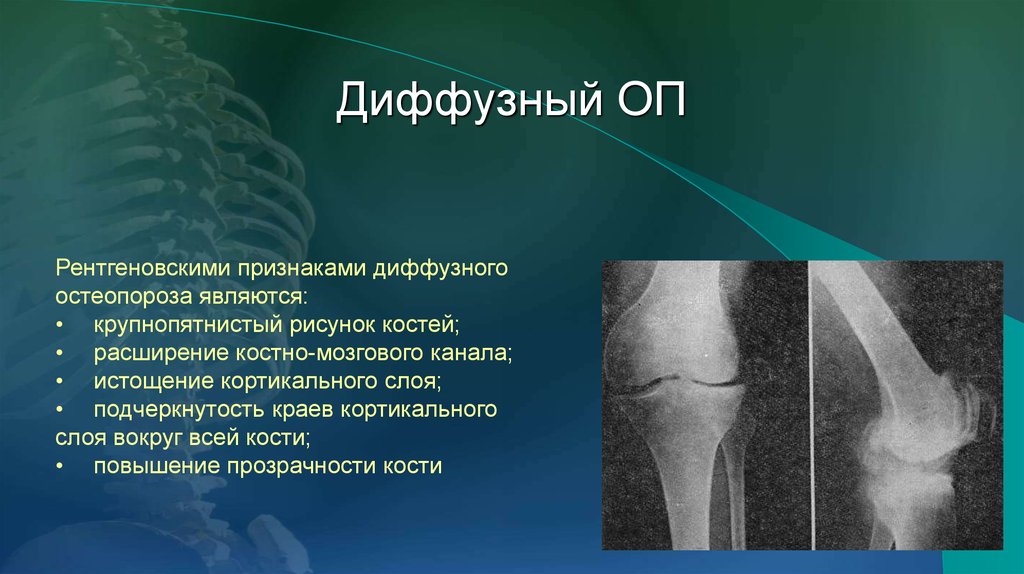

Рентгеновские снимки остеосклероза костной ткани